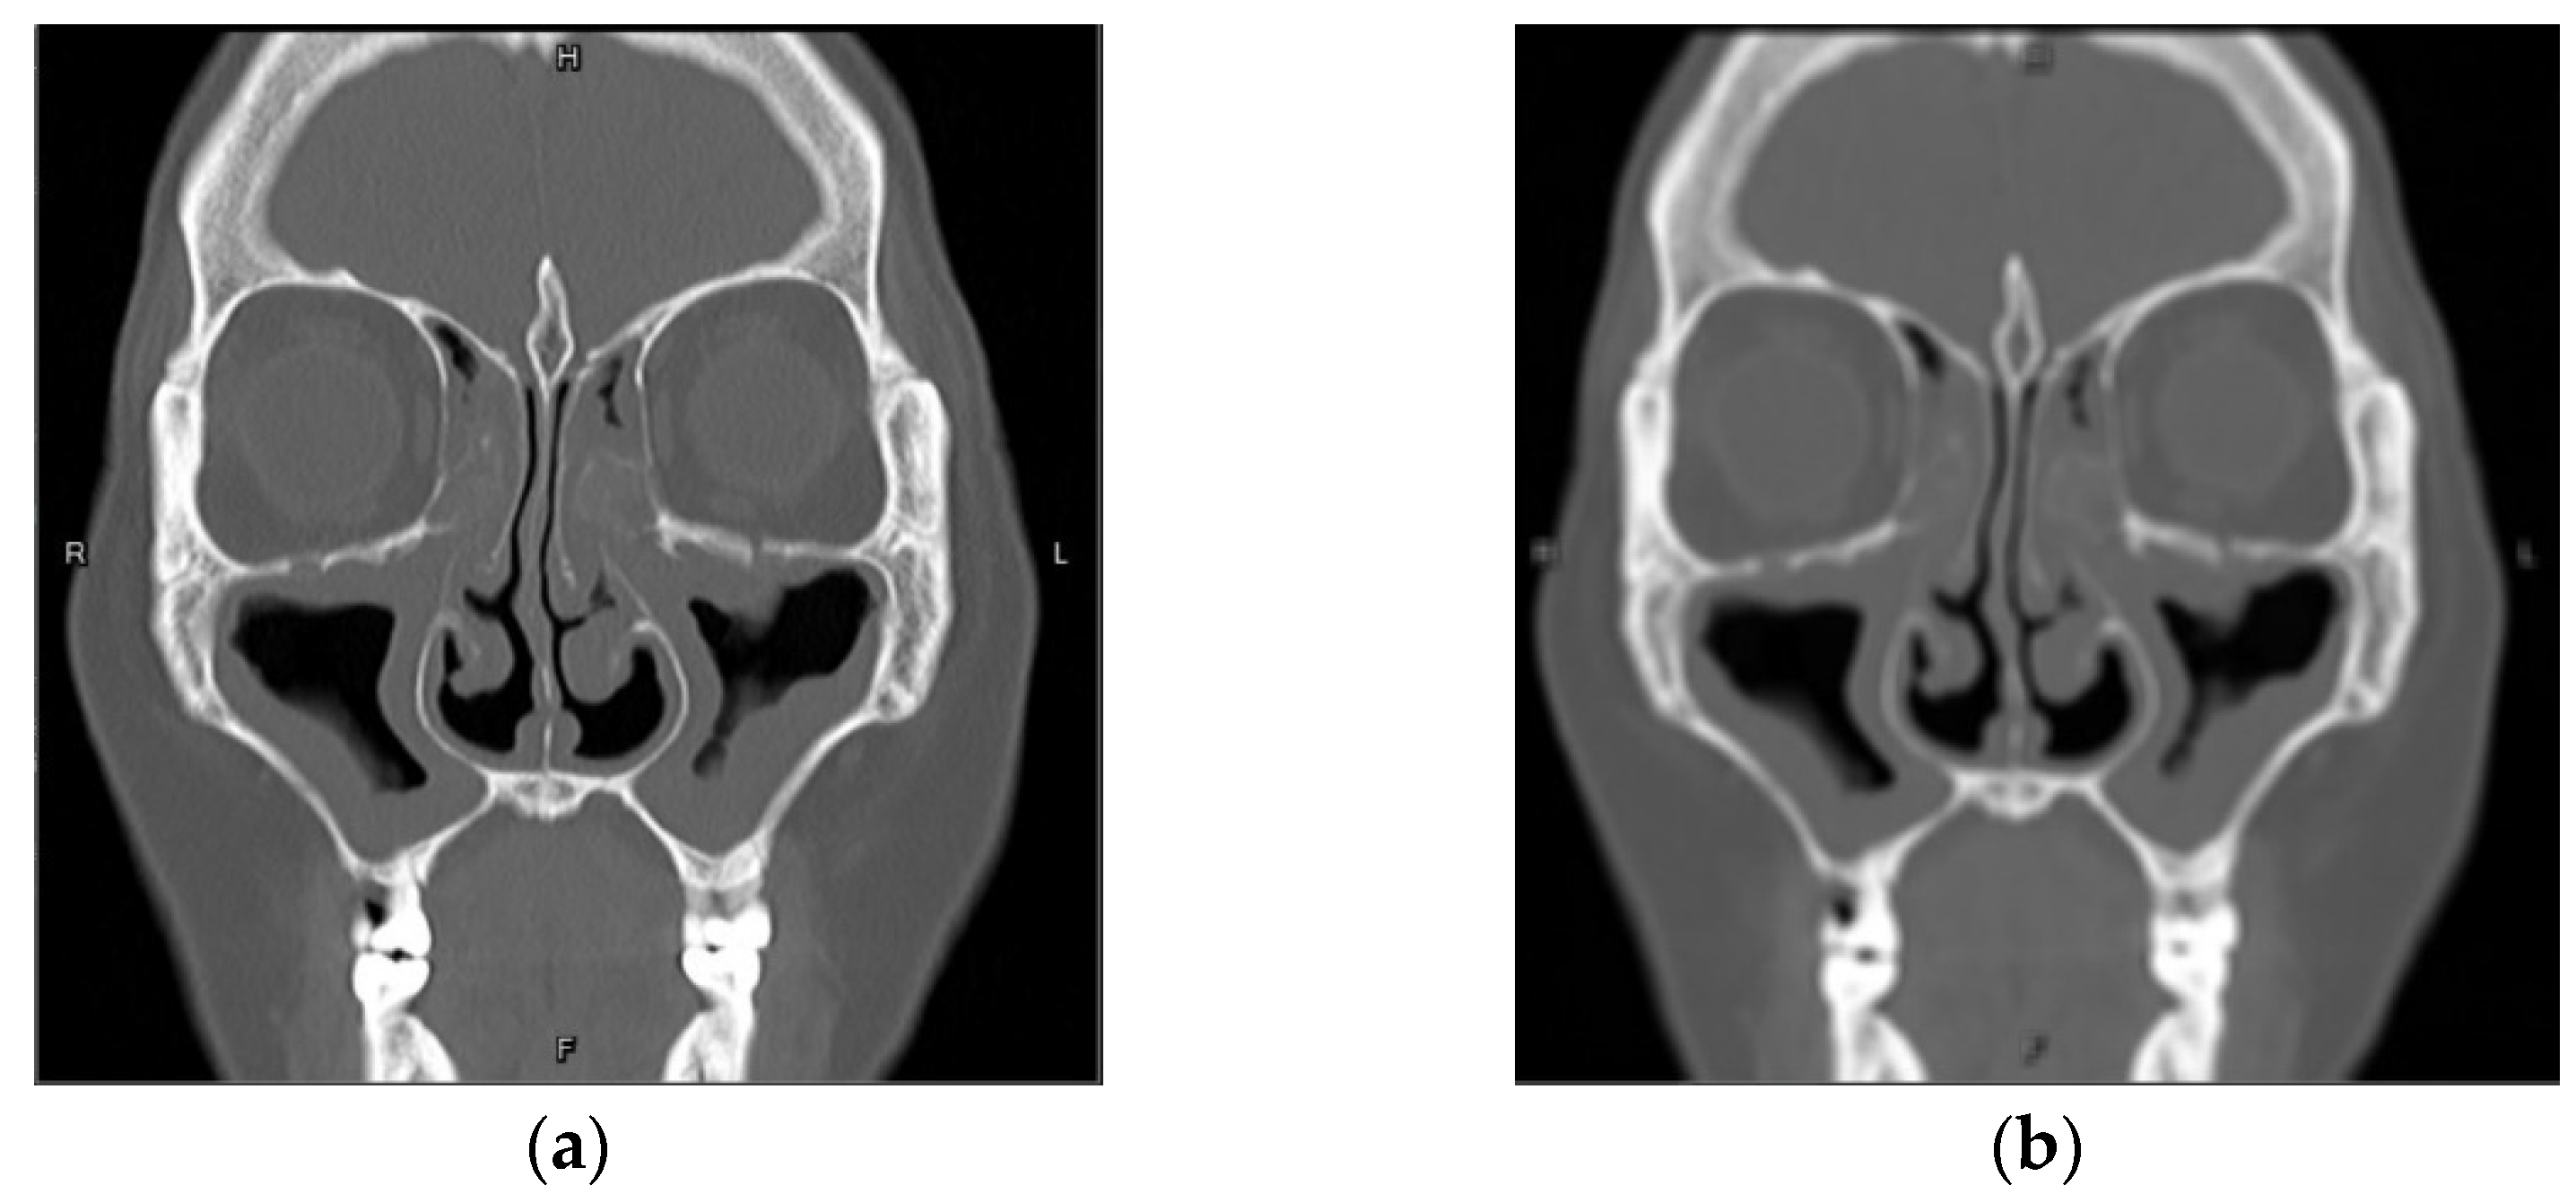

3.1.1. Gaussian Blur

3.1.2. Gaussian Noise